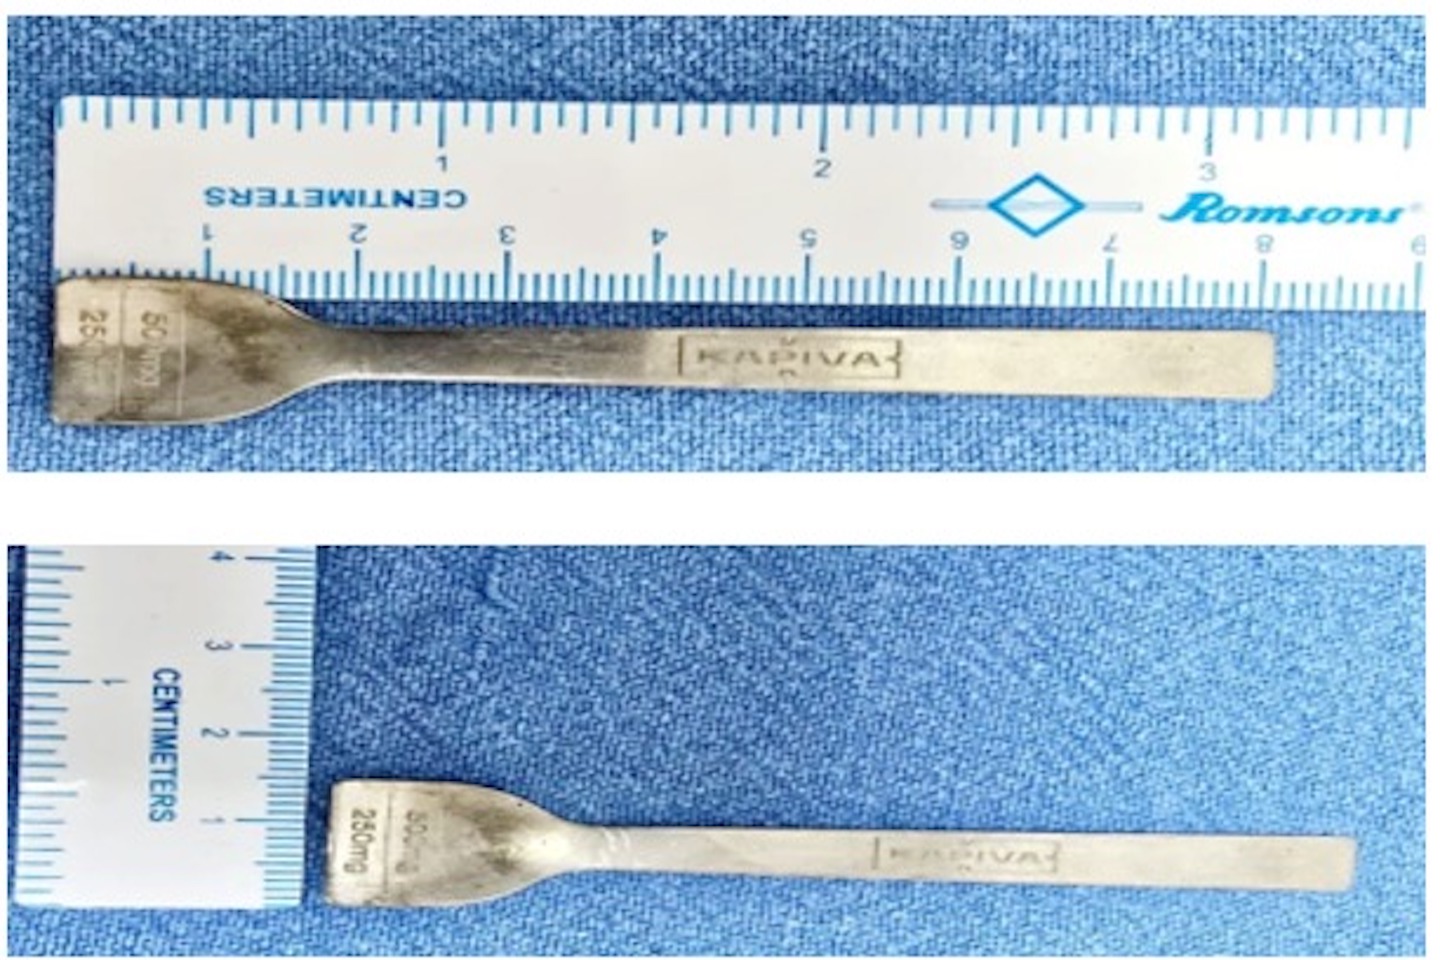

Image Caption: 8 cms Metallic Spoon successfully removed from 30-Year-Old Male’s Intestine

The Patient was referred to Fortis Shalimar Bagh’s Emergency department, after initial evaluation at multiple super-specialty hospitals in North Delhi. Upon presentation, the patient was vitally stable. Prompt diagnostic imaging, including an abdominal X-ray were conducted, which revealed a 8 cm long metallic spoon stuck at the upper part of his small intestine. An emergency upper gastrointestinal endoscopy was immediately planned and performed under anesthesia. Using forceps, the surgical team very carefully extracted the spoon from the stomach. Following the procedure, the patient was observed for 24 hours. He remained vitally stable throughout the post-procedural monitoring and was discharged in a healthy condition without any complications.

Giving details of the case, Dr Ramesh Garg, Senior Director & HOD, Gastroenterology, Fortis Hospital Shalimar Bagh said, “This was an extremely rare and challenging case. Ingesting a metallic object like a spoon can lead to serious complications, especially when it gets stuck in the upper part of the small intestine. Timely diagnosis and intervention were critical. Our team performed an emergency upper GI endoscopy under anesthesia, and with utmost precision, we were able to retrieve the 8cm-long spoon without causing any internal injury. The patient was closely monitored post-procedure and was discharged in a stable condition. This case highlights the importance of quick decision-making and multidisciplinary coordination in handling complex gastrointestinal emergencies.”

Deepak Narang, Facility Director, Fortis Hospital Shalimar Bagh said, “This case highlights Fortis Shalimar Bagh’s clinical expertise and the hospital’s ability to respond swiftly to rare and complex medical emergencies. The successful removal of an 8 cm metallic spoon through endoscopy in just 30 minutes is a testament to our advanced medical infrastructure, the skill of our specialists, and the strength of our emergency response protocols. We remain committed to delivering world-class care with precision, speed, and compassion.”